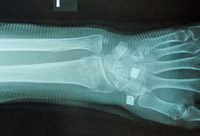

骨折(前腕骨遠位端部骨折の治療)

前腕骨遠位端部骨折の整復・固定

徒手整復で解剖学的整復位が得られています。

最も疼痛とリスクの少ないゼロ・ポジション法で整復しています。

固定は日常生活がしやすい内旋位固定を採用しています。